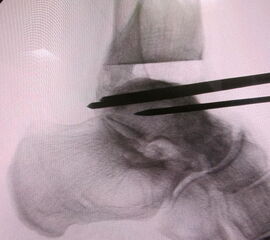

Osteosynthese eines intraoperativ frakturierten medialen Malleolus mit perkutanen Schrauben.

Abbildung 19

1. intraoperative Innenknöchelfraktur:

Mögliche Ursachen können eine zu weit medial plazierte Tibiakomponente oder eine zu weit mediale, nicht nach lateral konvergierende Sägerichtung im Rahmen der ventrodorsalen distalen Tibiaresektion sein (Abb. 19).